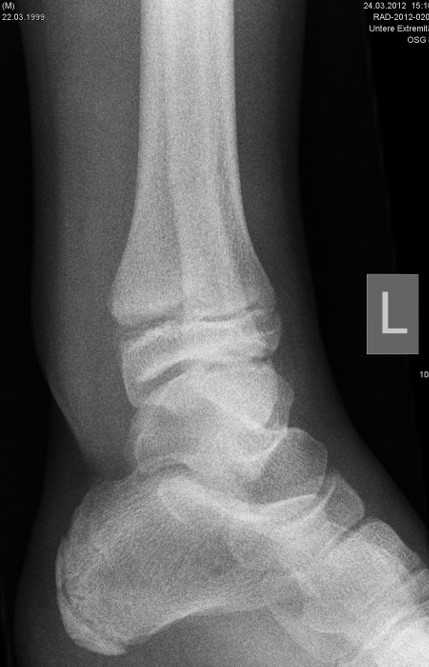

Fugengelenkfrakturen treten typischerweise vor dem 10. Lebensjahr auf, in einer Phase, in welcher die Wachstumsfugen noch weit offen sind. Dieser Frakturtyp betrifft fast ausschließlich den medialen Malleolus. Laterale Frakturen sind extrem selten, teilweise kommt es zu lateralen Bandverletzungen oder Fugenschaftfrakturen der distalen Fibula. Die Frakturlinie verläuft in einer Verlängerungslinie von der medialen Taluskante nach proximal. Häufig stellen sich Verletzungen des Innenknöchels im Röntgenbild schlechter dar, insbesondere wenn die Aufnahmen verdreht sind oder die Ebene der Fraktur bei geringer Dislokation verkippt zur Röntgenebene liegt. Besteht klinisch der geringste Hinweis auf eine Verletzung des Innenknöchels, muss aufgrund der Tragweite der Verletzung durch entsprechende Aufnahmen gegebenenfalls auch Schnittbildverfahren die Verletzung sicher diagnostiziert oder ausgeschlossen werden (Abb. 15).

„Kadiläsion“- Mediale Malleolarfraktur

Bei kindlichen Verletzungen des medialen Malleolus handelt es sich nach L. v. Laer um eine sogenannte Kadiläsion, d.h. eine Verletzung mit hohem Risiko eines schlechten Behandlungsergebnisses bei nicht korrekter Behandlung. Selbst bei optimaler Therapie ist das Risiko für spätere Wachstumsstörungen hoch, sodass diese Verletzungen nicht selten ein juristisches Nachspiel haben. Durch die Verletzung der wachstumsaktiven Zone kann es zu einem vorzeitigen Verschluss der Wachstumsfuge kommen, mit entsprechendem Fehlwachstum. Das Risiko eines vorzeitigen Verschlusses der Wachstumsfuge korreliert mit dem Ausmaß der Schädigung der wachstumsaktiven Zone. Ab dem 13. Lebensjahr wird das Risiko bei reduzierter Wachstumsaktivität zunehmend geringer.

Fugengelenkfrakturen können die Wachstumsfuge durchkreuzen (Abbildung 16a), ohne oder nur mit minimaler Beteiligung der Fuge sehr weit medial liegen (Abbildung 16b) oder durch die Fuge auslaufen (Abbildung 16c). Relevant für die Wachstumsprognose ist weniger die Form der Fraktur, sondern das Alter des Patienten zum Zeitpunkt des Traumas sowie das Ausmaß der Schädigung der Wachstumsfuge, wobei eine Korrelation mit dem Ausmaß der Dislokation besteht.